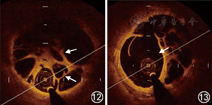

因规范药物治疗效果不佳,建议行PEA手术治疗,但患者考虑PEA术风险大,拒绝接受。建议患者行PTPA术并告知手术风险,患者及家属同意并签署手术同意书。行右心导管检查,具体数据见表1。术前根据术前肺通气/灌注检查结果提示右上肺和双下肺通气灌注缺损明显区域作为治疗部位,送入5F猪尾导管行双下肺野多体位选择性肺动脉造影确定病变血管确定病变部位(图9,图10,图11)。沿导丝送入6F MPD及6F JR3.5指引导管采用子母技术,将指引导管置于靶血管开口,送入贯穿导丝置于血管远端,沿导丝送入C7 Dragonfly OCT图像采集导管行OCT检查,可见管腔内大量网状结构,管腔狭窄(图12)。回撤OCT成像导丝,送入Pressurewire置于血管行压力测定,狭窄近端压力86/14/39 mmHg、狭窄远端压力16/7/11 mmHg,PPR(Pd/Pp):0.25。使用Cordis 3.0×15 mm球囊压力8~12个大气压维持8~10 s于病变部位扩张,扩张后造影血流明显改善,局部肺静脉回流明显增多增快。再次送压力导丝及OCT成像导丝,OCT成像导丝可见网格样结构被撕裂、管腔较前增宽(图13);分别测量压力,狭窄近端压力86/8/34 mmHg、狭窄远端压力33/8/14 mmHg,冠状动脉血流储备分数(fractional flow reserve,FFR)为0.44(图14,图15,图16,图17)。为避免再灌注肺水肿,初次在右上叶和双下叶肺野选择3条血管进行扩张,术毕拔除股静脉鞘管,加压包扎。术程顺利,患者无咯血、恶性心律失常。术后严密观察48 h,未发生灌注肺水肿。术后患者活动后气促症状改善。出院治疗方案为他达拉非10 mg,1次/d,贝前列素钠20 μg,3次/d,利伐沙班20 mg,1次/d。1个月后复查右心导管检查(表1),再次行右上及左下肺动脉球囊扩张(表2)。手术过程同上,术中和术后患者无咯血、无灌注肺水肿发生。术后患者活动后气促症状明显改善,6 min步行距离延长,行肺通气/灌注检查发现治疗后右上肺和左下肺灌注较前改善(图3,图4,图5,图6,图7,图8)。出院治疗方案为他达拉非10 mg,1次/d,利伐沙班20 mg,1次/d。